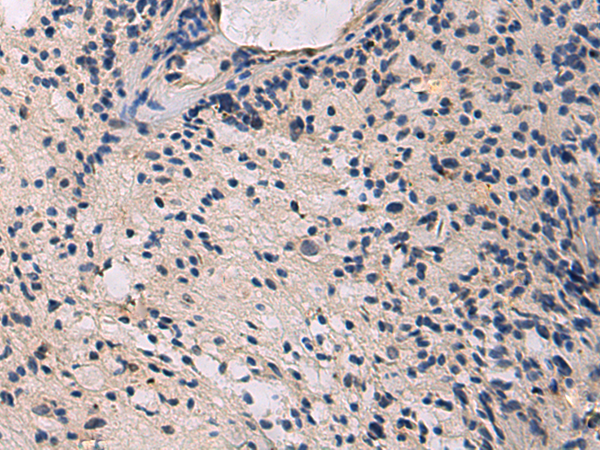

分类: 科研抗体货号: P13569别名: HEXO; THEX1; 3'HEXO应用: IHC反应种属: Human, Mouse, Rat